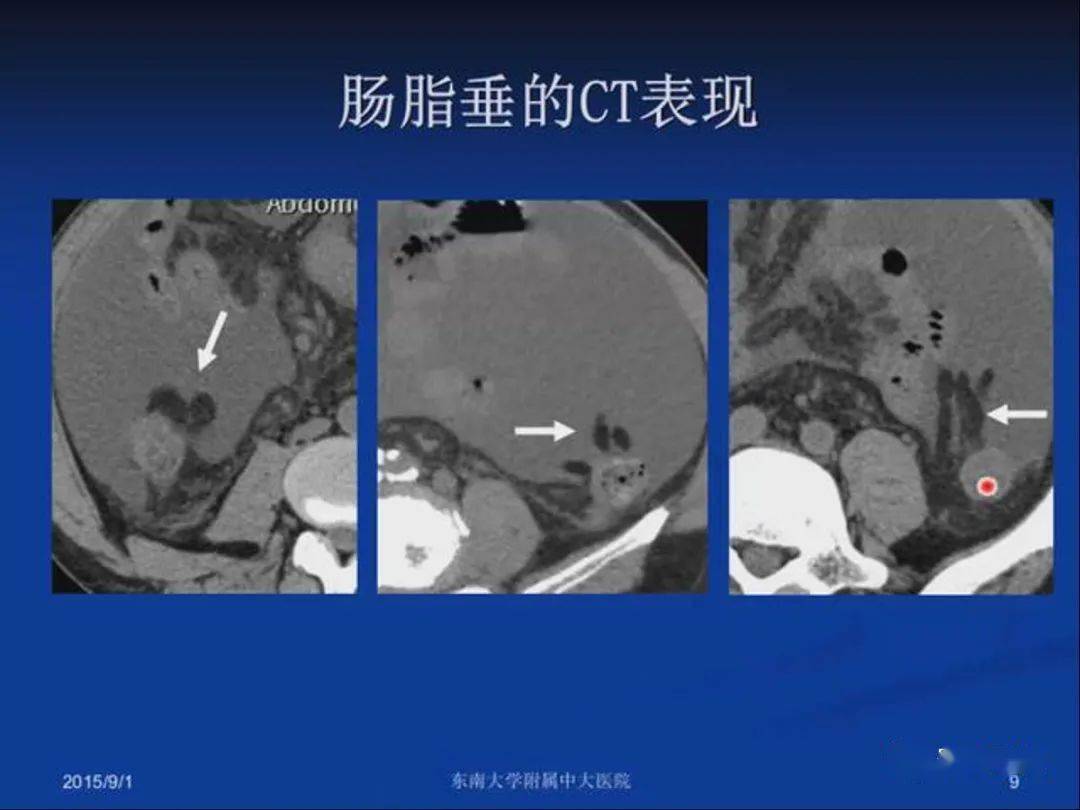

肠脂垂炎

急性原发性肠脂垂炎ct诊断与鉴别诊断